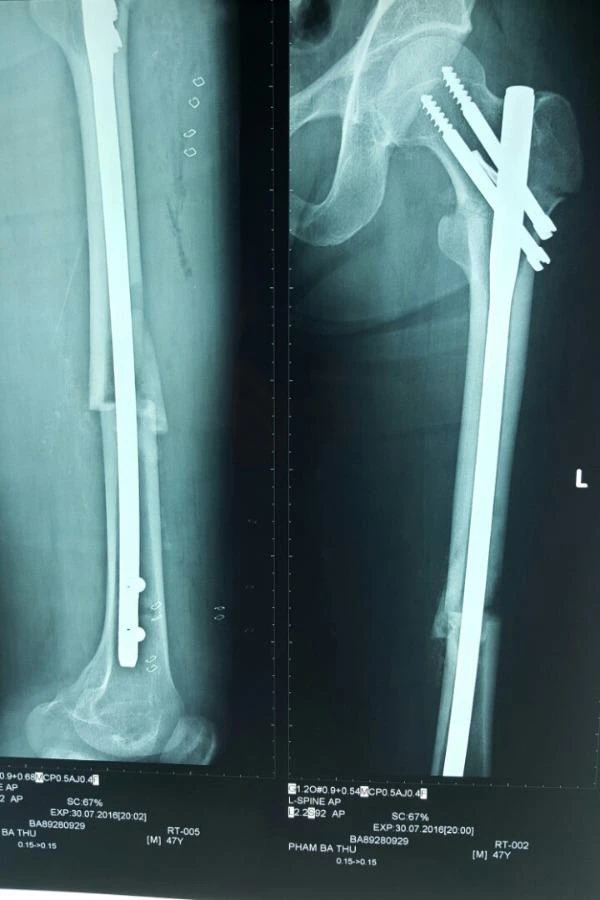

Kết quả chụp X-quang cho thấy bệnh nhân bị gãy kín nhiều mảnh 1/3 trên xương đùi phải và gãy kín hai tầng xương đùi trái. Các bác sĩ nhanh chóng điều trị tích cực cho bệnh nhân như hồi sức dự phòng chống sốc chấn thương, tiêm truyền thuốc giảm đau, dự trù máu và quan trọng là lên phương án xét nghiệm tiền phẫu để phẫu thuật cấp cứu kết hợp xương bệnh nhân.

Hai chân bệnh nhân lành lặn sau khi được đóng đinh nội tủy kín

Hai chân bệnh nhân lành lặn sau khi được đóng đinh nội tủy kín. Ảnh: CTV

Sau đó các bác sĩ tiến hành phẫu thuật bằng phương pháp tê tủy sống. Bác sĩ đóng đinh nội tủy kín xương đùi phải có chốt, sau đó đóng đinh nội tủy kín thân xương đùi trái. Sau hơn một giờ, ca phẫu thuật đã thành công. Các bác sĩ tiên lượng khả năng lành xương và phục hồi chức năng, nghề nghiệp cao.

Theo BS Khánh, ưu điểm của đóng đinh nội tủy kín xương đùi là bệnh nhân ít mất máu, không làm tổn thương thêm phần mềm và ít nhiễm trùng. Đóng đinh nội tủy kín giúp vững chắc ổ gãy, giúp bệnh nhân phục hồi vận động sớm, giảm nguy cơ tắc mạch.